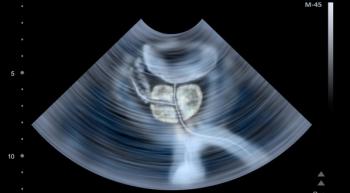

An imaging technique known as PSMA PET/CT can detect disease spread at diagnosis more effectively than conventional scans, helping doctors to prescribe appropriate treatments.